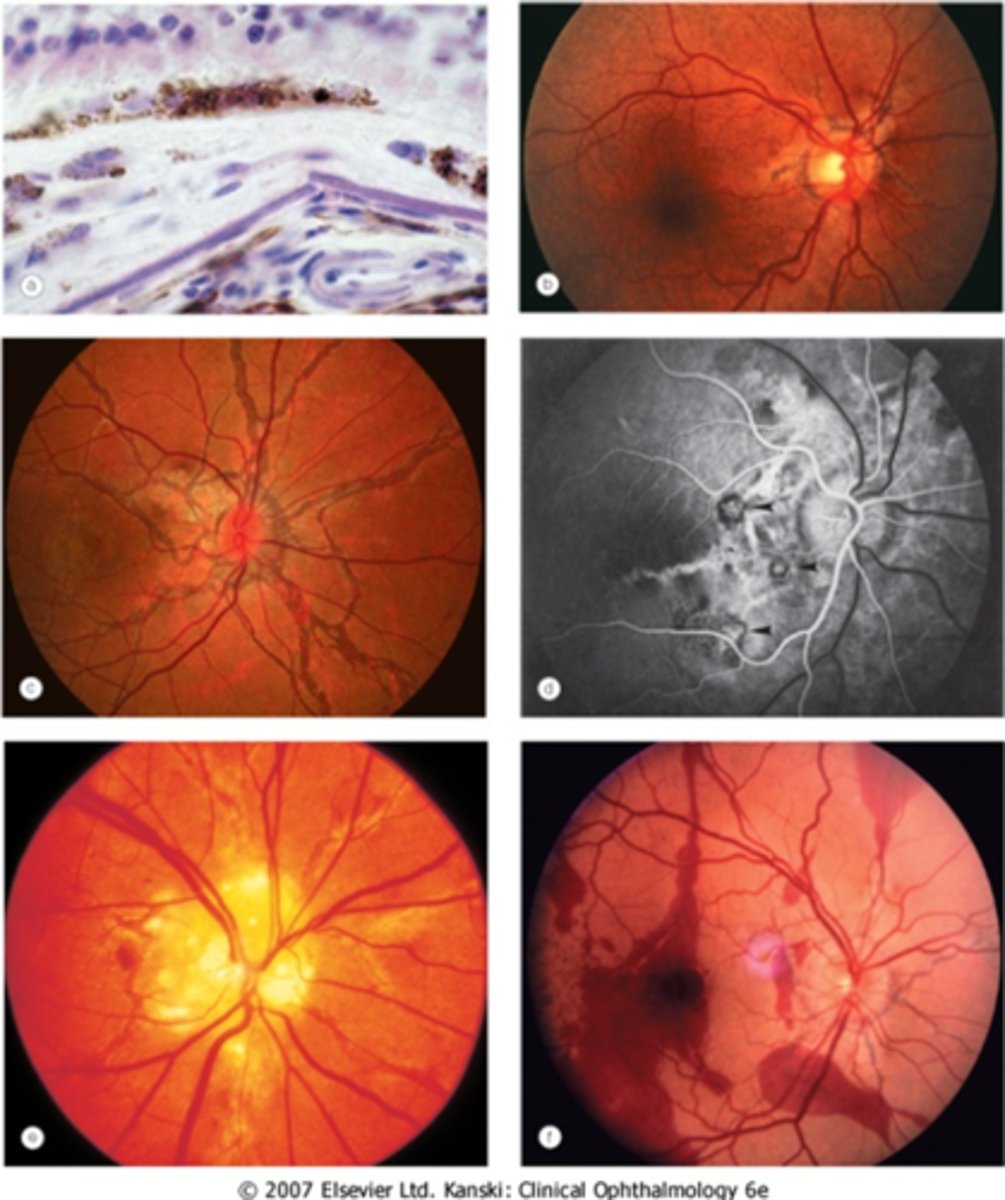

What finding of toxoplasmosis is seen in A/B?

retinitis turns into hazy scar with nerve pallor

What finding of toxoplasmosis is seen in C/D?

scarring overtime with VA loss/scotoma

What is seen in toxoplasmosis with OCT?

acute = retinitis = inflam, thickening of layers

acute = vitritis = dots and haze vitreous

chronic = necrotizing atrophy = scarring, thinning

What findings of toxoplasmosis are seen here?

retinal vasculitis

exudative scar

focal, hazy vitritis and retinitis

What findings of toxoplasmosis are seen here?

latent scars